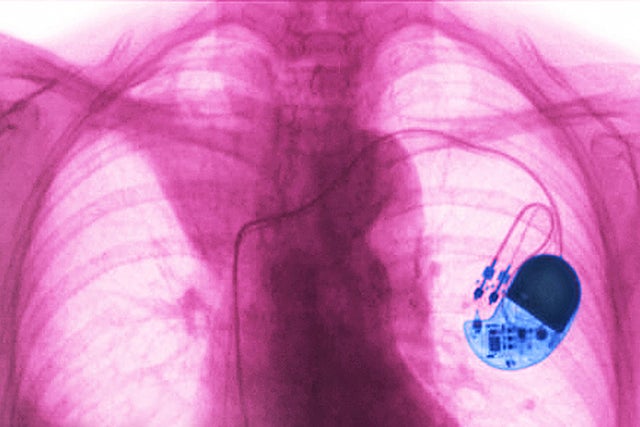

28. Inserting a pacemaker or defibrillator

Getting a pacemaker or defibrillator costs $58,281 on average. More than 200,000 pacemakers are implanted in the United States every year.

That's more than $11.6 billion in hospital bills, before insurance.

36. Removal of pacemaker or defibrillator

Having a pacemaker or defibrillator removed costs an average of $52,005.